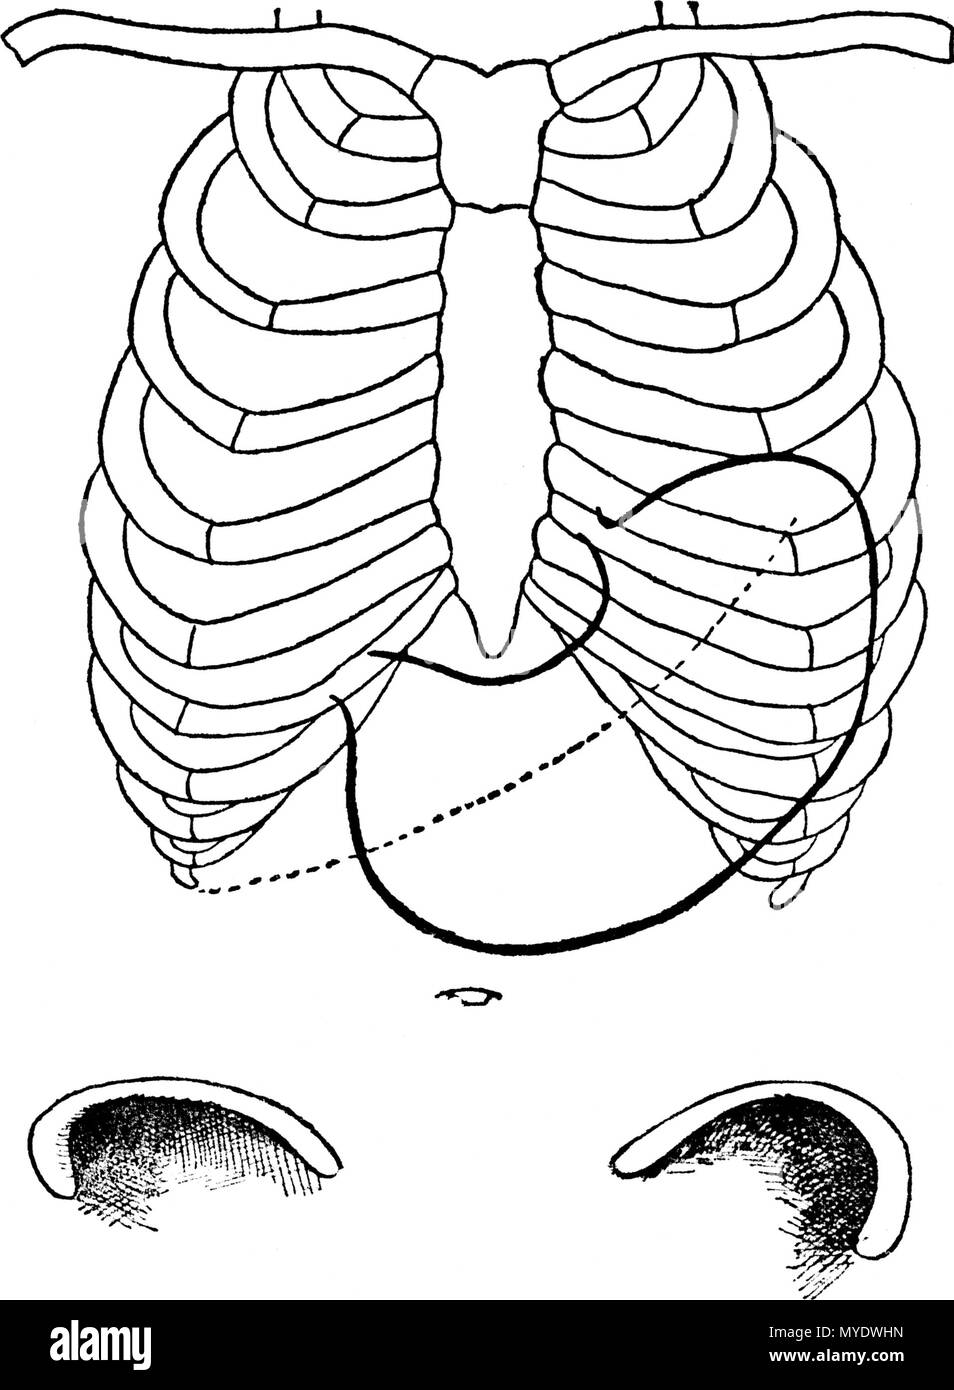

. Français : Figure 1 (d'après Boas); THORAX ET ESTOMAC NORMAUX; - - - - - - Bord inférieur du foie. Diaphragme. G Gros intestin. English: Figure 1 (according to Boas); NORMAL THORAXES AND STOMACH; - - - - - - lower Edge of the liver Diaphragm. G Large intestine . 1892. Le dr Eugène Chapotot 169 EstomacCorset page017 Stock Photohttps://www.alamy.com/image-license-details/?v=1https://www.alamy.com/franais-figure-1-daprs-boas-thorax-et-estomac-normaux-bord-infrieur-du-foie-diaphragme-g-gros-intestin-english-figure-1-according-to-boas-normal-thoraxes-and-stomach-lower-edge-of-the-liver-diaphragm-g-large-intestine-1892-le-dr-eugne-chapotot-169-estomaccorset-page017-image189004859.html

. Français : Figure 1 (d'après Boas); THORAX ET ESTOMAC NORMAUX; - - - - - - Bord inférieur du foie. Diaphragme. G Gros intestin. English: Figure 1 (according to Boas); NORMAL THORAXES AND STOMACH; - - - - - - lower Edge of the liver Diaphragm. G Large intestine . 1892. Le dr Eugène Chapotot 169 EstomacCorset page017 Stock Photohttps://www.alamy.com/image-license-details/?v=1https://www.alamy.com/franais-figure-1-daprs-boas-thorax-et-estomac-normaux-bord-infrieur-du-foie-diaphragme-g-gros-intestin-english-figure-1-according-to-boas-normal-thoraxes-and-stomach-lower-edge-of-the-liver-diaphragm-g-large-intestine-1892-le-dr-eugne-chapotot-169-estomaccorset-page017-image189004859.htmlRMMYDWHF–. Français : Figure 1 (d'après Boas); THORAX ET ESTOMAC NORMAUX; - - - - - - Bord inférieur du foie. Diaphragme. G Gros intestin. English: Figure 1 (according to Boas); NORMAL THORAXES AND STOMACH; - - - - - - lower Edge of the liver Diaphragm. G Large intestine . 1892. Le dr Eugène Chapotot 169 EstomacCorset page017

. Français : Figure 3 (d'après Rosenheim); ESTOMAC NORMAL, INSUFFLÉ; - - - - - - Bord inférieur du foie. 1892. Le dr Eugène Chapotot 169 EstomacCorset page022 Stock Photohttps://www.alamy.com/image-license-details/?v=1https://www.alamy.com/franais-figure-3-daprs-rosenheim-estomac-normal-insuffl-bord-infrieur-du-foie-1892-le-dr-eugne-chapotot-169-estomaccorset-page022-image189004865.html

. Français : Figure 3 (d'après Rosenheim); ESTOMAC NORMAL, INSUFFLÉ; - - - - - - Bord inférieur du foie. 1892. Le dr Eugène Chapotot 169 EstomacCorset page022 Stock Photohttps://www.alamy.com/image-license-details/?v=1https://www.alamy.com/franais-figure-3-daprs-rosenheim-estomac-normal-insuffl-bord-infrieur-du-foie-1892-le-dr-eugne-chapotot-169-estomaccorset-page022-image189004865.htmlRMMYDWHN–. Français : Figure 3 (d'après Rosenheim); ESTOMAC NORMAL, INSUFFLÉ; - - - - - - Bord inférieur du foie. 1892. Le dr Eugène Chapotot 169 EstomacCorset page022

. Français : Figure 19 (d'après Rosenheim). POSITION VERTICALE DE L'ESTOMAC, DE DIMENSIONS NORMALES. Sa situation pendant le gonflement, - - - - - - Bord inférieur du foie. 1892. Le dr Eugène Chapotot 196 EstomacCorset page069 Stock Photohttps://www.alamy.com/image-license-details/?v=1https://www.alamy.com/franais-figure-19-daprs-rosenheim-position-verticale-de-lestomac-de-dimensions-normales-sa-situation-pendant-le-gonflement-bord-infrieur-du-foie-1892-le-dr-eugne-chapotot-196-estomaccorset-page069-image187759258.html

. Français : Figure 19 (d'après Rosenheim). POSITION VERTICALE DE L'ESTOMAC, DE DIMENSIONS NORMALES. Sa situation pendant le gonflement, - - - - - - Bord inférieur du foie. 1892. Le dr Eugène Chapotot 196 EstomacCorset page069 Stock Photohttps://www.alamy.com/image-license-details/?v=1https://www.alamy.com/franais-figure-19-daprs-rosenheim-position-verticale-de-lestomac-de-dimensions-normales-sa-situation-pendant-le-gonflement-bord-infrieur-du-foie-1892-le-dr-eugne-chapotot-196-estomaccorset-page069-image187759258.htmlRMMWD4RP–. Français : Figure 19 (d'après Rosenheim). POSITION VERTICALE DE L'ESTOMAC, DE DIMENSIONS NORMALES. Sa situation pendant le gonflement, - - - - - - Bord inférieur du foie. 1892. Le dr Eugène Chapotot 196 EstomacCorset page069